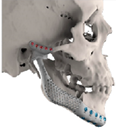

| ID | Age | eTMJR Class | Image | Reconstructed Structures | Fossa Materials | Condyle Materials | Screws and Fixation Holes |

|---|---|---|---|---|---|---|---|

| 1 | 71 | FT-M0 | ![]() | Temporal bone, aygomatic arch, glenoid fossa and condyle | Unalloyed titanium mesh temporal and zygomatic backing capping the UHMWPE fossa | Cobalt-chromiun-molybdenum alloy condylar head and Titanium alloy body | Skull component: 62.0 mm titanium screws. Manibular component: 82.7 mm titanium screws |

| 2 | 58 | FA-M0 | ![]() | Glenoid fossa with medial extension and condyle | Alloyed titanium backing capping the UHMWPE fossa | Cobalt-chromiun-molybdenum alloy condylar head and Titanium alloy body | Skull component: 52.0 mm titanium screws. Manibular component: 82.7 mm titanium screws |

| 3 | 41 | FO-M3 * | ![]() | Glenoid fossa and complete left hemimandible | Alloyed titanium backing capping the UHMWPE fossa | Cobalt-chromiun-molybdenum alloy condylar head and Titanium alloy body consisting of two interloching pieces | Skull component: 52.0 mm titanium screws. Manibular component: 112.7 mm titanium screws |

| 4 | 71 | FA-M3 | ![]() | Left zygomatic arch, glenoid fossa and complete left hemimandible extended to the right hemimandible ramus | Alloyed titanium zygomatic backing capping the UHMWPE fossa | Titantium alloy | Skull component: 82.3 mm titanium screws. Manibular component: 62.7 mm titanium screws |

| 5 | 26 | FA-M0 | ![]() | Temporal bone, zygomatic arch, glenoid fossa and condyle bilatreally | Alloyed titanium zygomatic backing capping the UHMWPE fossa | Cobalt-chromiun-molybdenum alloy condylar head and Titanium alloy body | Skull component: 172.0 mm titanium screws. Manibular component: 192.7 mm titanium screws |

| 6 | 54 | F0-M2 | ![]() | Glenoid fossa and complete right hemimandible | Alloyed titanium backing capping the UHMWPE fossa | Cobalt-chromiun-molybdenum alloy condylar head and Titanium alloy mesh body | Skull component: 52.3 mm titanium screws. Manibular component: 92.7 mm titanium screws |

| 7 | 63 | F0-M3 | ![]() | Glenoid fossa and complete left hemimandible | Alloyed titanium backing capping the UHMWPE fossa | Cobalt-chromiun-molybdenum alloy | Skull component: 52.3 mm titanium screws. Manibular component: 82.7 mm titanium screws |

| 8 | 24 | F0-M3 * | ![]() | Glenoid fossa and complete right hemimandible extended to the left hemimandible ramus | Cobalt-chromium-molybdenum alloy backing capping the UHMWPE fossa | Cobalt-chromiun-molybdenum alloy | Skull component: 52.3 mm titanium screws. Manibular component: 112.7 mm titanium screws |

| 9 | 52 | FT-M0 | ![]() | Temporal bone, zygomatic arch, glenoid fossa extended medially and condyle | Cobalt-chromium-molybdenum alloy backing capping the UHMWPE fossa | Cobalt-chromiun-molybdenum alloy | Skull component: 82.3 mm titanium screws. Manibular component: 82.7 mm titanium screws |